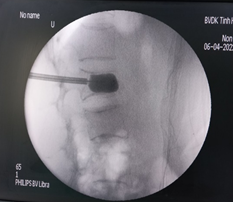

Bước 4: Tiến hành pha trộn xi măng theo tỷ lệ để chuẩn bị bơm

Bước 5: Đây là bước quan trọng nhất khi thực hiện kỹ thuật, xi măng sinh học sẽ được bơm qua kim định vị rỗng rỗng vào thân đốt sống bị xẹp. Tốc độ bơm phải chậm và được theo dõi chặt chẽ của bác sĩ thông qua C-arm và những biểu hiện lâm sàng của bệnh nhân như tình trạng đau hay cử động hai chân.

Bước 6: Để chắc chắn xi măng sinh học chỉ khu trú trong thân đốt sống, bác sĩ sẽ kiểm tra bằng C-arm hai bình diện thêm một lần nữa.

Sau khi thực hiện xong kỹ thuật, bác sĩ sẽ đánh giá toàn bộ quá trình thực hiện. Kỹ thuật thành công khi xi măng lan tỏa trong thân đốt sống bị xẹp, không có tình trạng thoát xi măng ra bên ngoài đốt sống. Sau khoảng 4-5 giờ xi măng đông cứng hoàn toàn, người bệnh có thể đi lại bình thường và tình trạng đau đốt sống được cải thiện rõ ràng.